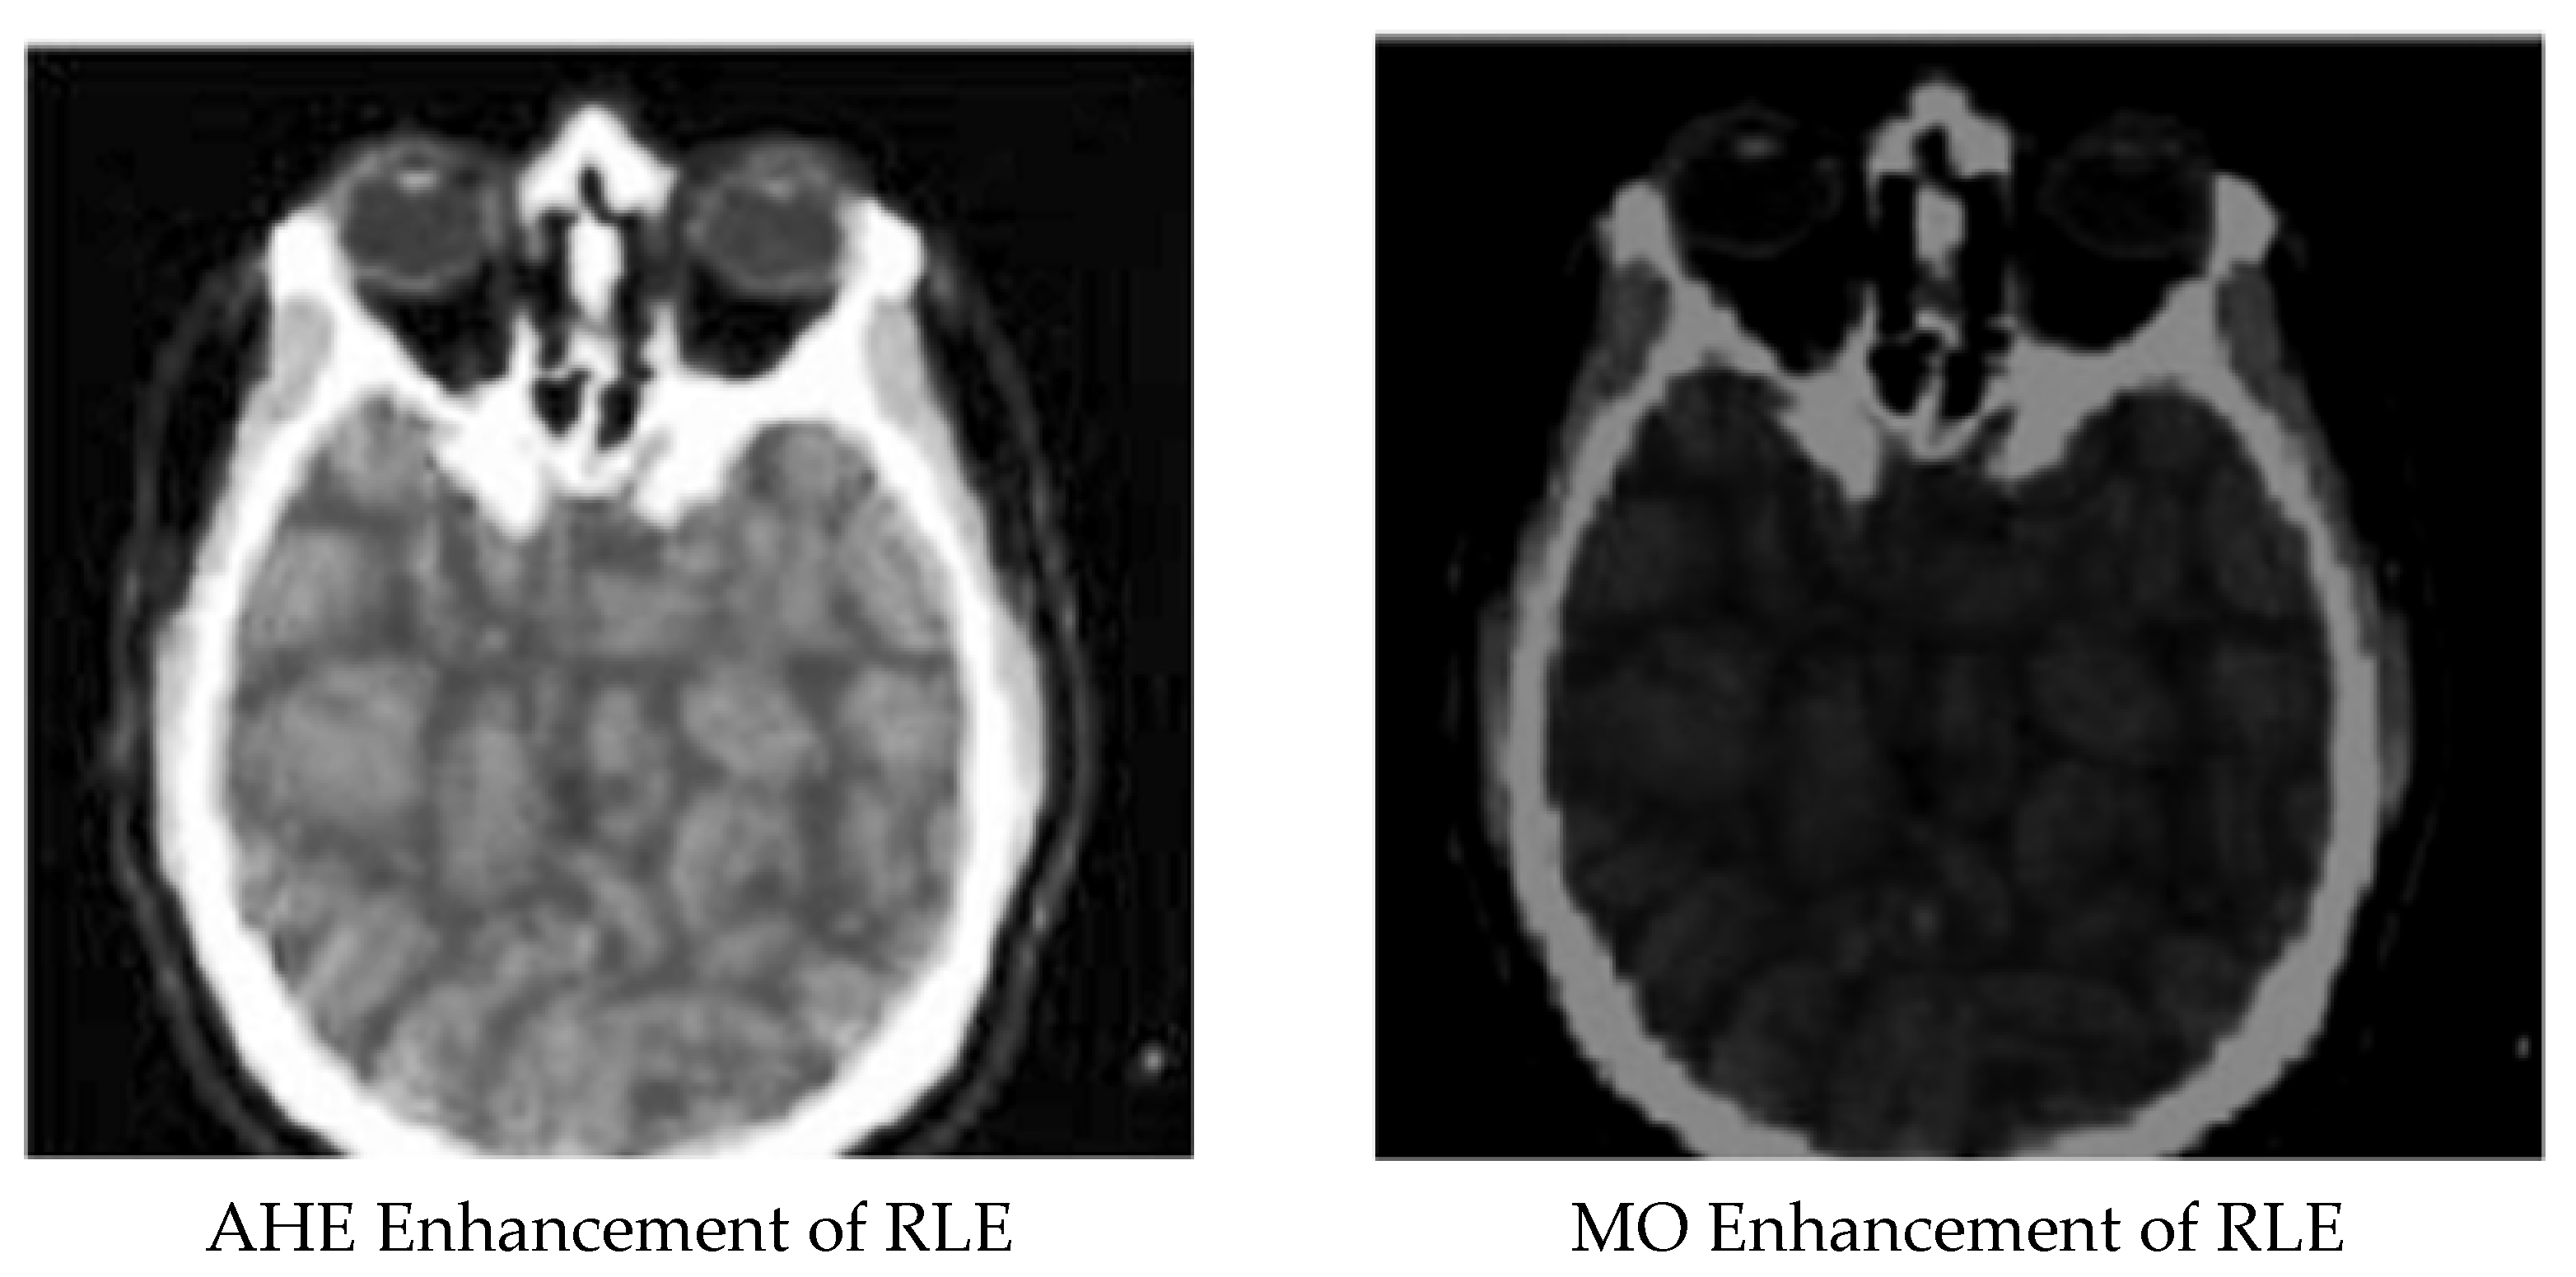

Enhanced and Compressed Output

5. Discussion

| 9 | RLE compressed image | 0.48970346 | 0.299972986 | 43.72625764 |

| 10 | AHE enhancement for RLE compressed image | 0.87101654 | 0.000629014 | 70.50874365 |

| 11 | MO enhancement for RLE compressed image | 0.81224123 | 0.001335176 | 69.85366112 |